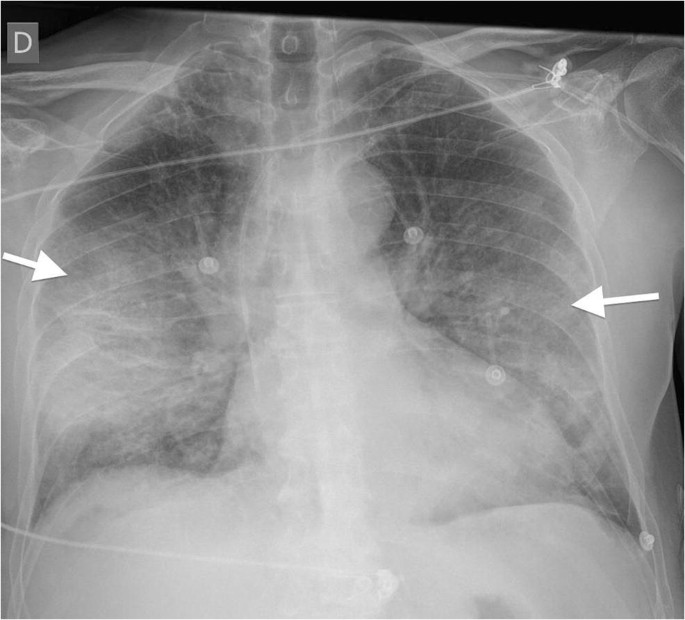

Covid19